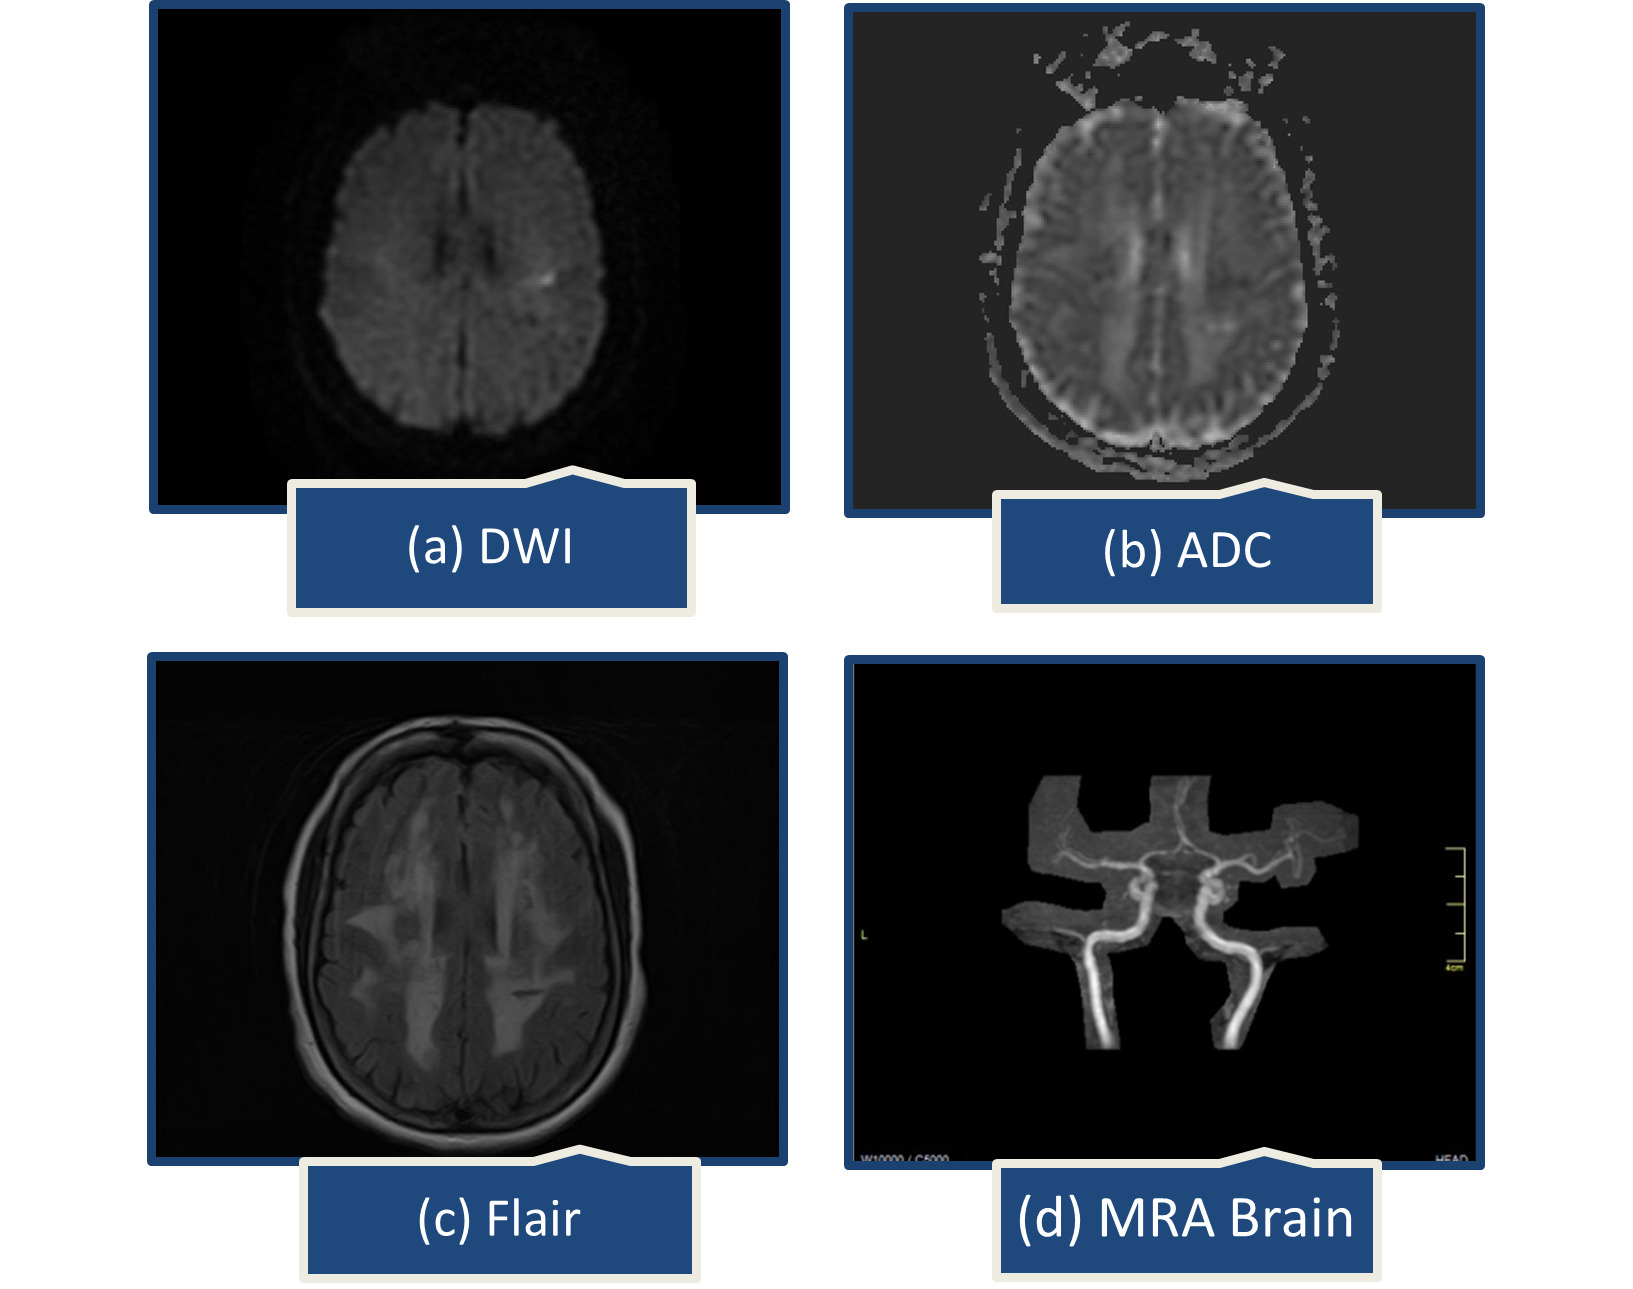

A year later, she presented with abrupt speech problems and ataxia. She could speak, but had trouble finding words, which had spontaneously improved by the time she arrived at the emergency room. There were no complaints of body weakness, numbness, or facial deviation. On examination, her Glasgow coma scale was 15/15, all reflexes intact, muscle power was MRC grade 5/5 in all limbs, National Institutes of Health Stroke Scale (NIHSS) was 2, one point for language causing mild-to-moderate aphasia; some obvious loss of fluency, without significant limitation on form of expression and one point for dysarthria causing mild-to-moderate dysarthria; patient slurred at least some words which could be understood with some difficulty. Brain computed tomography (CT) scan showed extensive confluent hypodensities in bilateral periventricular white matter. On brain MRI, a small acute ischemic infarct in left centrum semiovale and extensive confluent fluid attenuated inversion recovery (FLAIR) bright signal foci were noted in bilateral periventricular and subcortical white matter representing chronic microvascular ischemic changes (Figure 1).